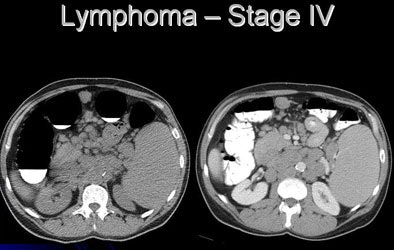

![]() |

| At VC, extracolonic CT images suggested abnormal mesenteric lymphadenopathy. Stage 1 lymphoma was confirmed at surgery. |